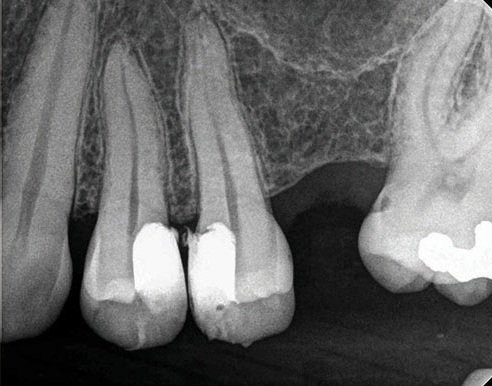

(5.) Preoperative radiograph of tooth No. 19 following a pulpectomy procedure that was complicated by an intraoperative furcal perforation.

Figure 5

(6.) Postoperative radiograph showing immediate perforation repair using MTA followed by complete obturation.

Figure 6

(7.) One-year follow-up periapical and bitewing radiographs demonstrating the absence of apical pathosis or furcal pathosis at the site of

the perforation.

Figure 7

(8.) One-year follow-up periapical and bitewing radiographs demonstrating the absence of apical pathosis or furcal pathosis at the site of

Figure 8

Bioceramic materials, including MTA, offer a predictable means to repair iatrogenic furcal and lateral root perforations (Figure 5 through Figure 8).16 Overall, studies favor the use of MTA over other nonbioceramic materials for perforation repair,17,18 which is attributable to its superior seal. In addition, its inherent biocompatibility and osteoconductivity facilitates the repair of localized hard tissue damage. The key to successful perforation repair, regardless of the material utilized, is in the immediacy of its performance and completion before bacterial cross-contamination and inflammation-mediated bone loss can occur.17